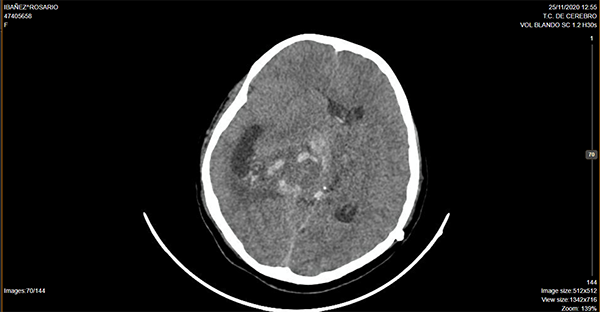

Caso ilustrativo n°2: Houkin tipo 2(Figura 2)

Paciente de 14 años de edad, consultó por deterioro del sensorio, cefalea y vómitos, se realizó tomografía computada de cerebro donde se evidenció lesión ocupante de espacio supratentorial intraventricular. Se programó cirugía, se realizó exéresis parcial. Cursa postoperatorio intubada en terapia intensiva presentado descompensación hemodinámica a las 24 hs, imagen por tomografía computada de cerebro que evidencia sangrado intratumoral, se reexplora la lesión, paciente evoluciona desfavorablemente.

Se consideró Houkin tipo 2, ya que el evento adverso estuvo relacionado con el procedimiento quirúrgico pero no era ni esperable ni evitable.

Figura 2: Imagen por Tomografía Cerebral computada donde se observa lesión ocupante de espacio intraventricular centroencefálica, con sangrado intratumoral y desvío de línea media.